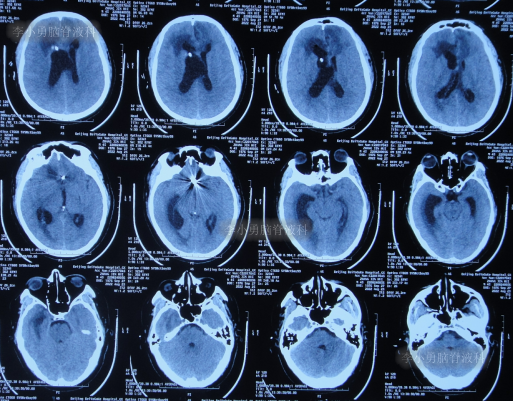

入院时头颅CT示脑室扩张,动脉瘤栓塞术后(图-11)。

图-11:入院时头颅CT

入院后次日进行了脑室外引流术(图-12)。

图-12:2022年8月25日术后头颅CT